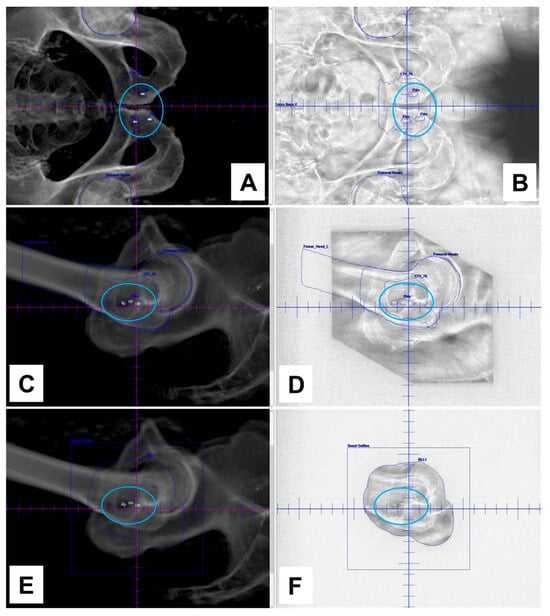

3.4. Visibility of NOVA Markers in a Clinical Case